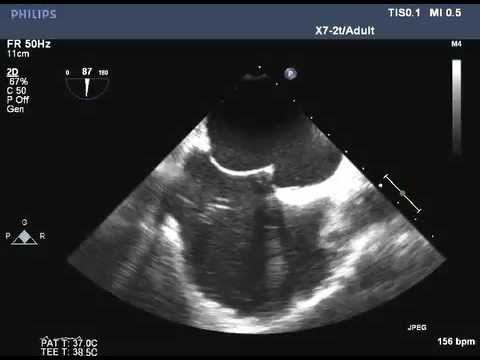

Video 7.1

Video 7.1 Bicaval view from transesophageal echocardiography showing the atrial septum.